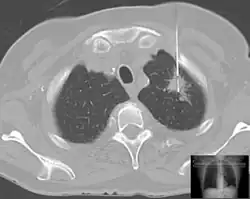

Biopsia pulmonar percutánea o transparietal o transpleural

Se realiza generalmente con control radiológico. Existen diversos métodos como la biopsia aspirativa, la biopsia con aguja cortante y el taladro ultrarrápido de aire comprimido. La principal indicación es en aquellos tumores periféricos de difícil o imposible acceso por otros procedimientos. Con el perfeccionamiento de la biopsia transbronquial, con control radiológico y la PAAF, los casos en los que es preciso realizar esta técnica son muy escasos. En más del 80 % de los tumores se obtienen muestras suficientes para establecer el diagnóstico del tumor. Los inconvenientes son el neumotórax que ocurre en el 15 al 55 %, a veces muy graves o la diseminación pleural de células tumorales. Las contraindicaciones son enfisema bulloso, sospecha de quiste hidatídico, sospecha de aneurisma o fístula arteriovenosa, neumonectomía contralateral, diátesis hemorrágica y cor pulmonar grave.